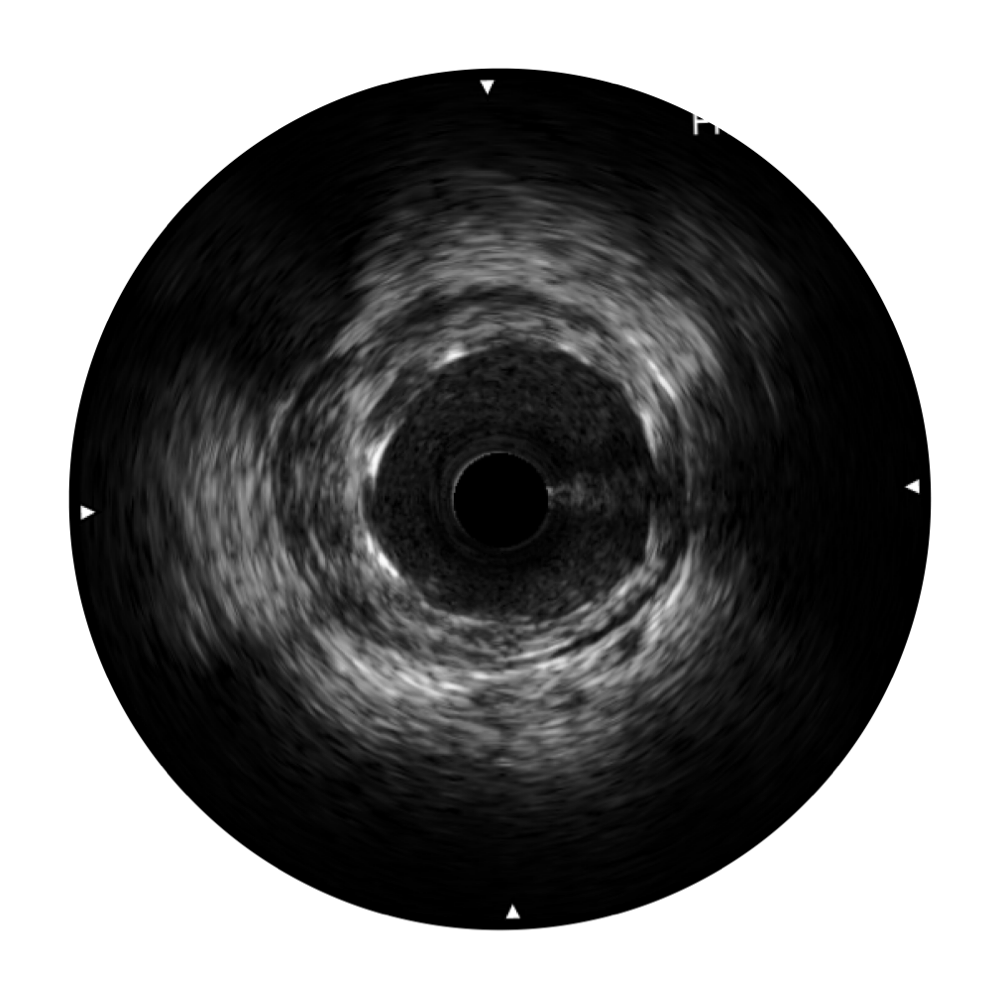

• 传统IVUS图像

对比传统IVUS导管成像,百老汇电子游戏官网宽频IVUS图像的近场支架梁显影更细腻,远场中膜外血管仍清晰可辨,兼顾远中近,兼顾分辨力与穿透深度